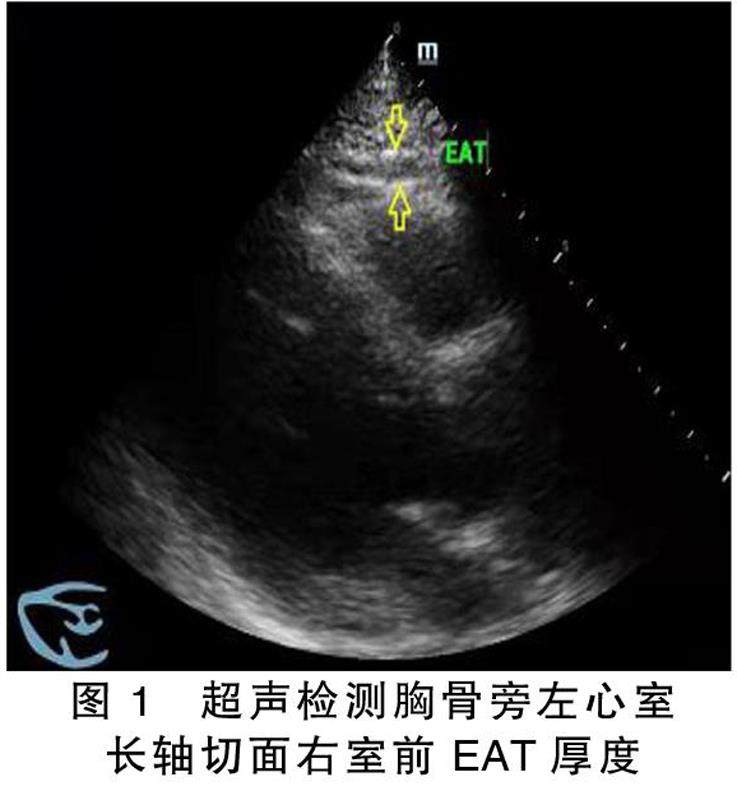

摘要目的:探讨心外膜脂肪组织(EAT)厚度与射血分数保留的心力衰竭(HFpEF)的关系。方法:选取2021年12月—2022年4月就诊于沧州市中心医院心内科并诊断为HFpEF的62例病人作为研究组,选取同期于同一所医院体检中心进行健康体检者71名作为对照组。收集并比较研究对象的一般资料、血常规及生化指标结果,心脏超声检测左房内径、左室舒张末期内经、EAT厚度,采用Logistic回归分析筛选HFpEF的危险因素。(剩余8097字)

心外膜脂肪组织厚度与射血分数保留的心力衰竭的关系